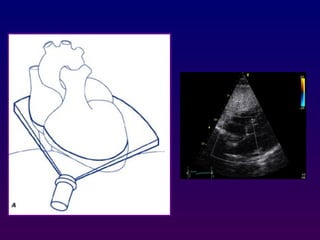

Subcostal four-chamber

The subcostal views may be obtained either with the

patient in supine position with the knees bent to

relax the abdominal musculature. The transducer is

positioned immediately below or to the right of the

xiphoid process. This allows visualization of the

basal, mid, and apical right ventricle, the inferior

interventricular septum, and anterolateral left

ventricular walls. The interatrial septum is oriented

nearly perpendicular to the ultrasound beam.

Subcostal four-chamber The subcostalviews may be obtained either with the patient in supine position with the knees bent to relax the abdominal musculature. The transducer is positioned immediately below or to the right of the xiphoid process. This allows visualization of the basal, mid, and apical right ventricle, the inferior interventricular septum, and anterolateral left ventricular walls. The interatrial septum is oriented nearly perpendicular to the ultrasound beam.